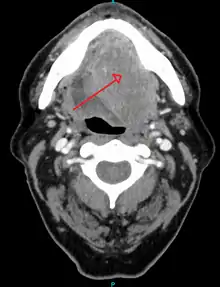

Head and neck cancer

A large head and neck squamous-cell carcinoma of the tongue as seen on CT imaging

About 90%[4] of cases of head and neck cancer (cancer of the mouth, nasal cavity, nasopharynx, throat and associated structures) are due to SCC.